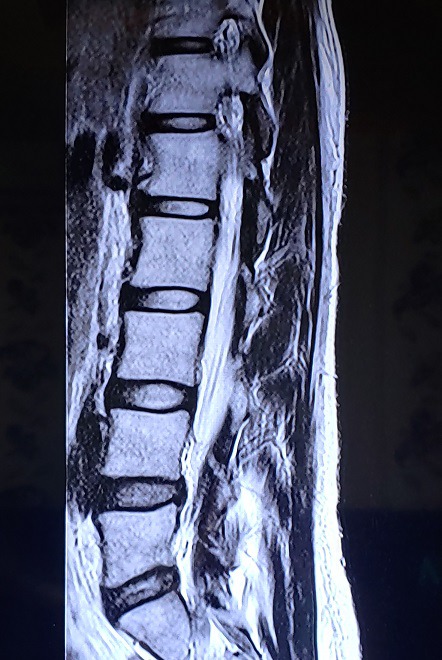

2017.12.30 경추 회전변위/ 요추 회전변위 / 디스크돌출/ 2020.1.10 역C자 목

당시에는 제가 몇 번 디스크라고 말도 안 해주셔서 몰랐는데 이번 지도사 과정을 배우면서 스스로 알게됐네요. 4-5번 디스크 돌출과 약간 요추후만..으로 보이네요.

뭐 아무튼 디스크도 다 문제없이 운동을 한다고 하고, 저는 특히 목이 허리보다 더 심하게 아팠었기 때문에 웨베를 사서 매일 한시간씩 C무브를 했습니다. 고개를 좌우로 움직이는게 통증이 아닌 시원함이 될 때까지 한달이 걸린 것 같아요. 웨베를 무리없이 베고 자는데까지는.. 잘 모르겠어요. 어느 순간부터 꿀잠 자고 있었으니까요 ㅎㅎ 그래도 적어도 4-5개월은 걸린 듯 합니다. 어쨌든 초반의 SNPE는 매일매일 자기 전에 C무브만 1시간 이상을 했어요. 다시 회사를 다니면서 틀어진 몸을 막 쓰다보니 C뭅이라도 안 하면 잠을 잘 수가 없었어요. 구르기는 거의 못했고, 일하는 중간중간 1번만 매일 3번 이상 하면서 자세를 잡아갔죠. 기지개 대신 1번을 계속 했어요.